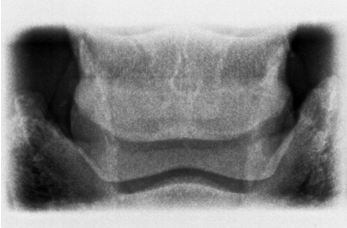

• what view is this?

dorsopalmar